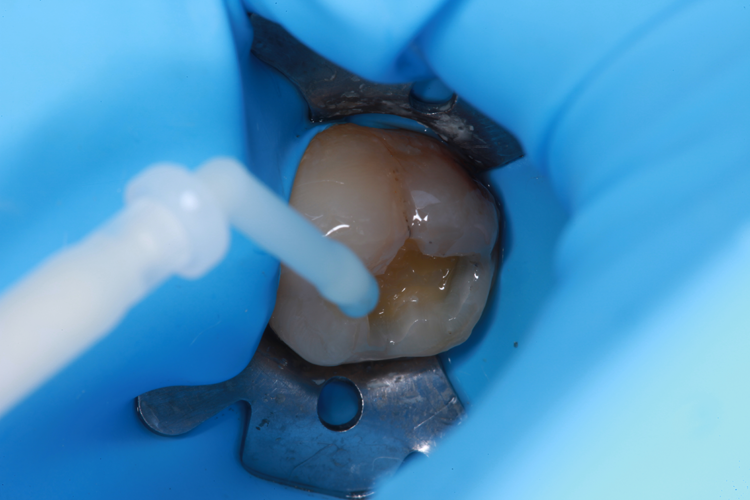

The enamel was etched for 20 seconds with Select HV from BISCO (Fig. 3), and ALL-BOND UNIVERSAL (BISCO) was applied (Fig. 4).

Fig. 3: Enamel etched for 20 seconds with Select HV. Fig. 4: ALL-BOND UNIVERSAL applied.